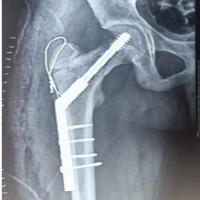

A 77-year-old male with right knee pain was diagnosed with advanced OA. In pursuit of relief, the patient underwent GAE at another hospital. Following the procedure, the patient developed swelling, increased pain, and skin discoloration, necessitating readmission to the same hospital for vascular observation and pain control. Redness, swelling, and pain subsided over a period of 7 days, and the patient was discharged from the hospital (Fig. 1). After a 6-month recovery period, owing to persistent osteoarthritic knee pain, the patient sought further treatment options at our hospital. Upon consultation with our radiologists, an arteriogram was performed 1 year after embolization, and it was ascertained that the genicular arteries remained patent (Fig. 2). Consequently, a decision was made to proceed with total knee arthroplasty to manage OA. During arthroplasty, bone samples of bone cuts from the weight-bearing distal femur and proximal tibia were sent for histopathological examination, and the results were negative for osteonecrosis (Fig. 3). The post-operative period involved meticulous monitoring of complications such as wound dehiscence, tissue necrosis, and infection. Fortunately, aside from the mild erythema observed around the knee a week after the procedure, which did not require any treatment, the wound healed well without any complications, with standard rehabilitation of same-day walking, and ROM exercise could be initiated (Fig. 4 and 5). After 1 year of follow-up, the patient experienced relief of knee pain and achieved a knee range of motion of up to 0°–120° and back to his day-to-day activities, indicating a successful outcome following total knee arthroplasty (Fig. 6 and 7).